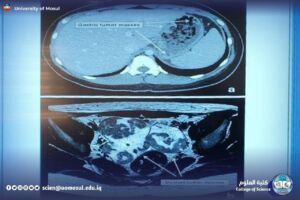

خلال الدورة تم شرح المبادئ الأساسية للتصوير الطبي مثل التباين، الدقة، مبدء عمل كل جهاز، فيزيائيه الجهاز، وكيفيه قراءة الصور ناتجه من جهاز. ثم الانتقال لعرض أهم الأجهزة التالية بشكل مبسط:

CT: شرح لكيفية أخذ مقاطع متعددة، وفكرة الـHU، ودوره في تصوير الدماغ والبطن والرئة.